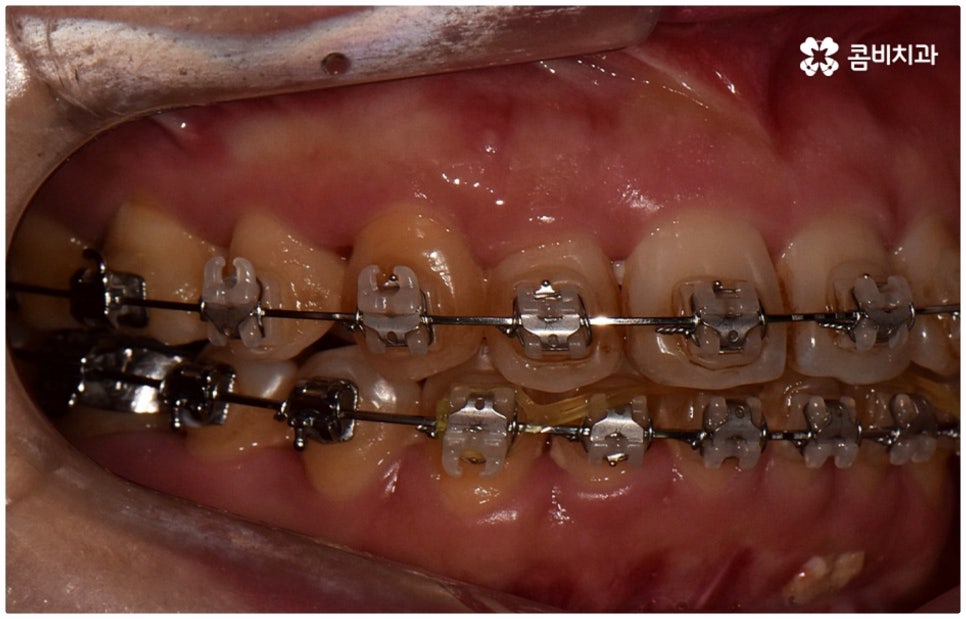

출처 아카이브 열기위아래 치열이 제대로 맞물리지 않으면 음식물을 씹을 때 어려움을 느끼거나 발음상 문제가 생길 수 있습니다. 이것을 부정교합이라고 하며, 그 종류는 상악과 하악의 골격적인 전후방 관계를 기준으로 1급, 2급, 3급으로 나눌 수 있어요. 위아래 어금니는 잘 맞물리는데 치열이 조금씩 삐뚤어져 있거나 치아 사이가 벌어져 있는 등 살짝씩 어긋난 부정교합은 1급, 위 어금니가 더 앞으로 나가있는 부정교합은 2급 (ex. 돌출입), 그리고 아래 어금니가 더 앞으로 나가있는 부정교합은 3급 (ex. 주걱턱) 으로 분류하게 되는데 이 중 오늘 살펴보려고 하는 것은 부정교합 3급에 해당하는 반대교합에 대한 거예요.

정상적인 교합은 윗 앞니가 아래 앞니를 살짝 덮는 정도로 윗니가 조금 더 앞으로 나와 있으면서 위아래 치아가 어금니까지 잘 맞물리는 것을 말하는데 반대교합은 위아래 앞니가 거꾸로 물리는 증상을 보이기 때문에 저작 활동 및 발음 조성이 원활하지 않게 되며 반대교합교정 등 적절한 치료를 받지 않고 방치할 경우 점점 더 주걱턱이 강화되는 쪽으로 뼈가 성장할 수 있어 될 수 있는 대로 빠른 시일 내에 원인을 분명하게 알아보고 그에 맞는 치료를 받는 것이 중요하다고 할 수 있어요.

골격적인 원인이 아니라면 위턱과 아래턱의 위치나 크기에는 이상이 없는데 치아의 맹출 각도 및 방향의 문제로 인해 치아가 반대로 맞물리게 된 치성 반대교합에 해당하는 경우라고 할 수 있는데요. 그 원인으로는 선천적인 치열의 문제 (아래턱 앞니 치축이 앞으로 기울거나 위턱 앞니 치축이 뒤로 들어감), 유치가 너무 빨리 빠지고 영구치가 자리를 제대로 잡지 못해 생긴 문제, 후천적인 습관 (혀를 내밀거나 손톱을 깨무는 등 치열에 좋지 않은 영향을 주는 행위를 지속적으로 반복) 으로 인한 문제 등등을 살펴볼 수 있으며, 보통 이런 경우 앞니 4~6개 치아 일부에 국한된 문제이기 때문에 보다 빠르고 간단하게 교정 치료가 가능하므로 꼭 성장기에 치료를 시작하지 않고 성인이 된 후라고 해도 비교적 쉽게 개선이 될 수 있습니다.

교정 치료가 생물학적 반응을 이용하는 것이다 보니 성장기에 진행하면 치아 이동 및 회복 속도 등에 장점이 있는 것은 분명하지만 그렇다고 해서 성인 이후 중장년 분들이 교정 치료를 받을 수 없는 것은 아니며 이미 많은 분들이 도움을 받고 계신 만큼 이에 대해서 한 번 고려해 보시면 좋을 거예요. 혹시 성장기 이후로는 양악 수술 등으로만 치료가 가능한 것이 아닐까 생각하셔서 부담스럽게 느끼셨던 분들이라면 지레 겁을 먹고 불편함을 그대로 방치하시기 보다는 검진 및 상담을 통해 적극적으로 이를 해결해 보시길 권유드리고 있어요.

물론 원인과 정도에 따라 외과적인 방법이 필요하신 분들도 있을 수 있지만 교정을 통해 얼마든지 치료가 가능한 경우도 있으며 앞서 말씀드렸던 것처럼 발전된 교정 기술 및 특수 미니스크류 등의 장치 개발을 통해 턱의 방향을 조금씩 회전시켜 원거리 치아 이동을 유발하는 것이 가능해졌기 때문에 예전에는 한계가 있었던 부정교합 케이스도 개선될 여지가 늘어나고 있습니다. 꼼꼼하게 검진을 받으시고 자신의 상황에 맞는 교정 치료를 무리하지 않게 진행하신 후 철저하게 사후 관리를 해주시면 보다 오랜 기간 동안 건강하게 고른 치열을 유지하면서 생활하실 수 있을 거예요.